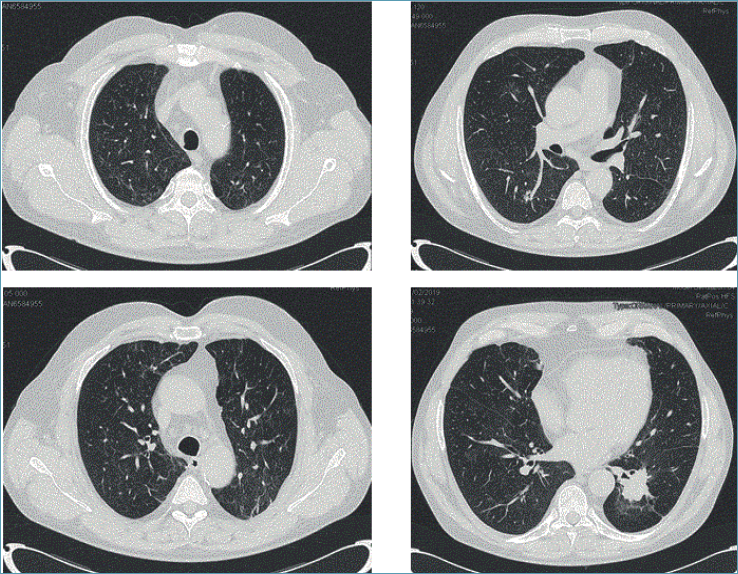

I primi report di polmoniti da immunoterapia (ICI-ILD) hanno descritto lo spettro delle possibili manifestazioni radiologiche e i differenti pattern di polmoniti interstiziali 15,32,34, in accordo con la classificazione proposta dalle linee guida ATS/ERS 35, utilizzata per tutti i tipi di polmoniti da farmaci 19,31. Di recente, a causa della grande diffusione dei nuovi farmaci oncologici e quindi, del crescente rischio di tossicità polmonare, la Fleischner Society 9 ha creato nuove linee guida che indirizzano il clinico nella diagnosi precoce e nella gestione dei paziente in terapia oncologica. In accordo con la letteratura, il pattern di ILD più comune è quello della polmonite organizzativa (OP), caratterizzato da opacità consolidative e ground glass, spesso migranti, tipico di tutti i tipi di tumore e caratteristico per più farmaci (Figg. 1 e 2).

Figura 1.Paziente di 56 anni, maschio, adenocarcinoma polmonare stadio IV, PDL 1 70%, in trattamento con pembrolizumab. Multipli, irregolari addensamenti parenchimali a distribuzione prevalentemente peribroncovascolare; concomitano multiple areole a vetro smerigliato peribronchiolari diffuse. Quadro compatibile con OP (Paziente in cura presso AOU Careggi, Firenze).

Figura 2.Reperti HRTC dopo trattamento con steroide.